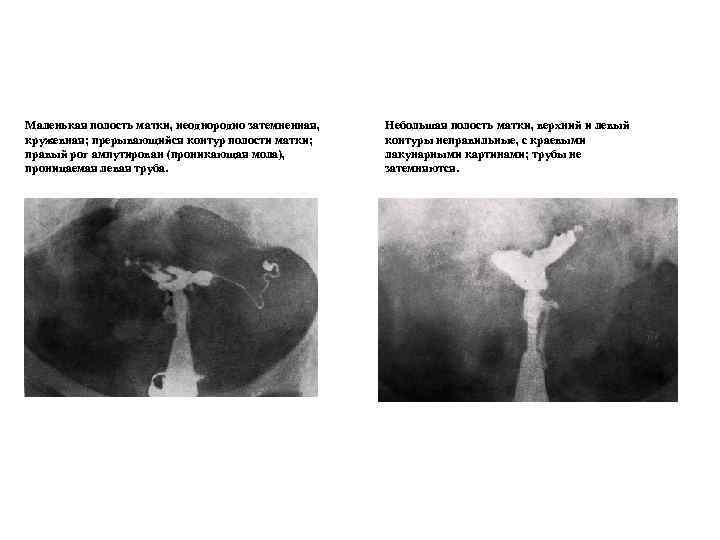

Рентгенологические методы исследования Рентгенологические методы остаются широко распространенными методами исследования, это, прежде всего, относится к гистеросальпингографии (ГСГ). ГСГ давно используется в гинекологической практике для установления проходимости маточных труб, выявления анатомических изменений в полости матки, спаечного процесса в области малого таза. Для выполнения ГСГ пользуются водно-растворимыми рентгеноконтрастными веществами (веротраст, уротраст, верографин и т. д. ). Эти вещества благодаря своим структурным особенностям дают четкое изображение щелей, лакун, выбуханий и ниш в стенке матки. Все это имеет важное диагностическое значение для выявления внутреннего эндометриоза тела матки (аденомиоза), небольших миоматозных узлов и полипов эндометрия. Произведение ГСГ на 5 -7 день менструального цикла уменьшает частоту ложноотрицательных результатов. Устье маточных труб в первую фазу цикла широко открыто и не препятствует проникновению контрастного вещества из полости матки в маточные трубы.

Маленькая полость матки, неоднородно затемненная, Небольшая полость матки, верхний и левый кружевная; прерывающийся контур полости матки; контуры неправильные, с краевыми правый рог ампутирован (проникающая мола), лакунарными картинами; трубы не проницаемая левая труба. затемняются.